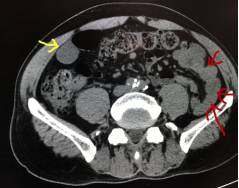

如上图1:黄色箭头指的就是胃,这是一个没有喝水,没有充盈好的胃,我们可以看到箭头指的胃壁是明显厚的,正常的胃壁也是厚的,但是如果里面隐藏长着东西,刚好胃壁这里有个小胃癌,那就没办法诊断了,就会导致漏诊。

再看看图2:这个患者胃肠道准备做得很好,我们可以看到一样是黄色箭头里指的胃,里面装的都是水,胃壁被填充成薄薄的一层了,如果长东西胃壁异常增厚,那么就可以一目了然了。